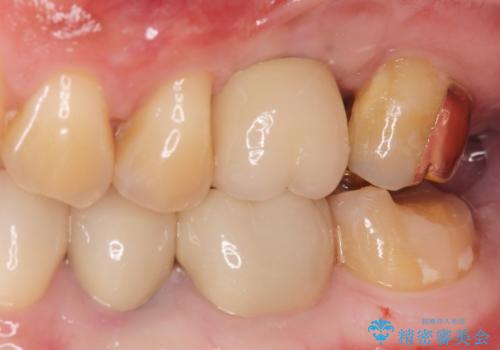

適合の良いゴールドクラウンが入りました。

患者様に満足して頂けました。

ゴールドは適合が良く、割れる心配もありません。

また、虫歯になるリスクも銀歯と比べて低くなります。